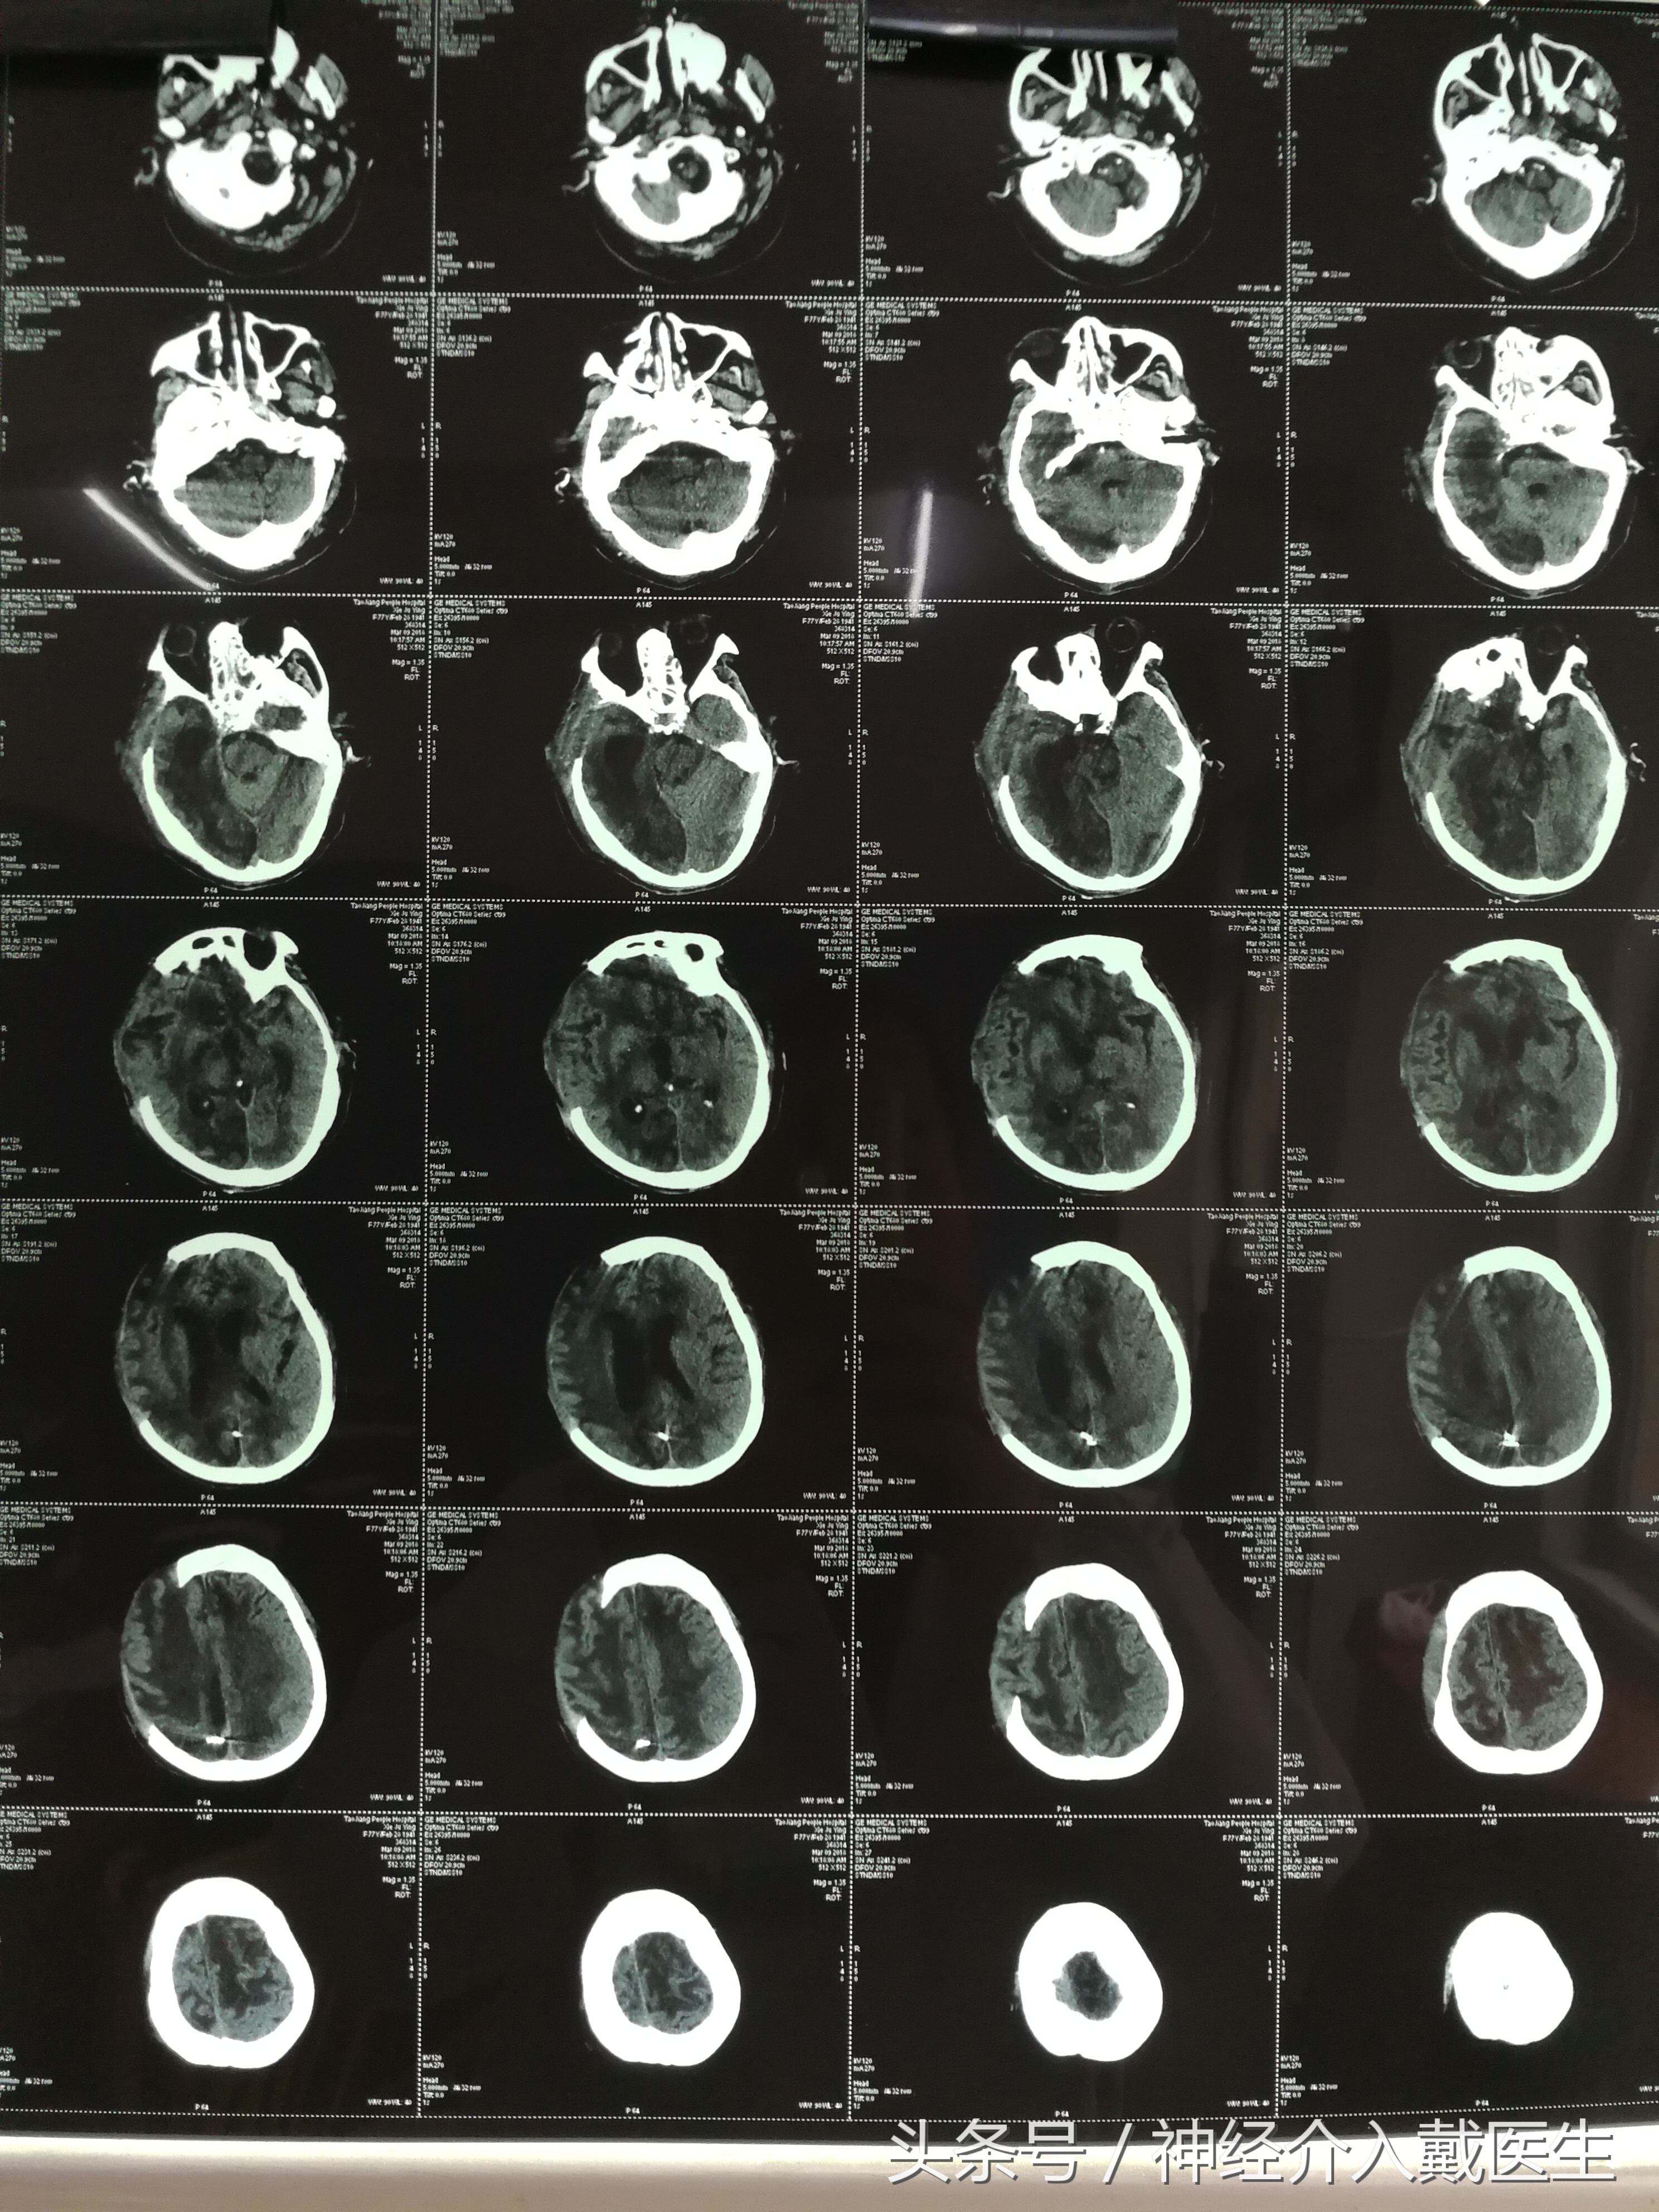

那是发生在去年12月23日晚上十一点多,随着救护车的一阵紧急呼叫,一名重型脑出血患者被送往重症监护室。谢某,女,77岁,因为突然神志不清1小时,呕吐2次,小便*禁失**入院。既往高血压病史20余年,血压最高220/120mmHg,冠心病10余年,平时低于一般活动即感胸闷,气促。入院时候血压230/120mmHg,双侧瞳孔已经散大,头部CT:右侧顶叶脑出血,脑内血肿,右侧额颞顶部硬膜下血肿,蛛网膜下腔积血及脑室出血,脑疝。

胸部CT:动脉粥样硬化,左心增大,肺部感染,心电图:偶发房早,多发室早,凭经验,脑内出血量这么大,超过70ml,这么快就发生脑疝的,人基本上难救的,向家属交代病情的危险性,做手术清除血肿和去骨瓣减压上唯一可能延长生命的方法,但是因为基础病变多,颅内出血多,手术风险是相当大的,可能死于手术台上,最好的结局就是植物人。病人的女儿是个老师,听我们说了之后,坚决要求尽最大努力抢救,并且和远在深圳的弟弟电话商量后,更是态度坚决,不管什么结局家属都能够接受,留下一个躯壳也行,并且一再保证,即使病人死了,也不会怪医生,让医生不要有后顾之忧。经过一个晚上的手术后,病人安全的下了手术台,

又经过多少个日日夜夜医生护士的努力,生命体征趋于平稳,目前已经转入普通病房,因为当时脑出血后导致的脑损伤太重,最近复查的头部CT,几乎满脑子都是缺血性改变。